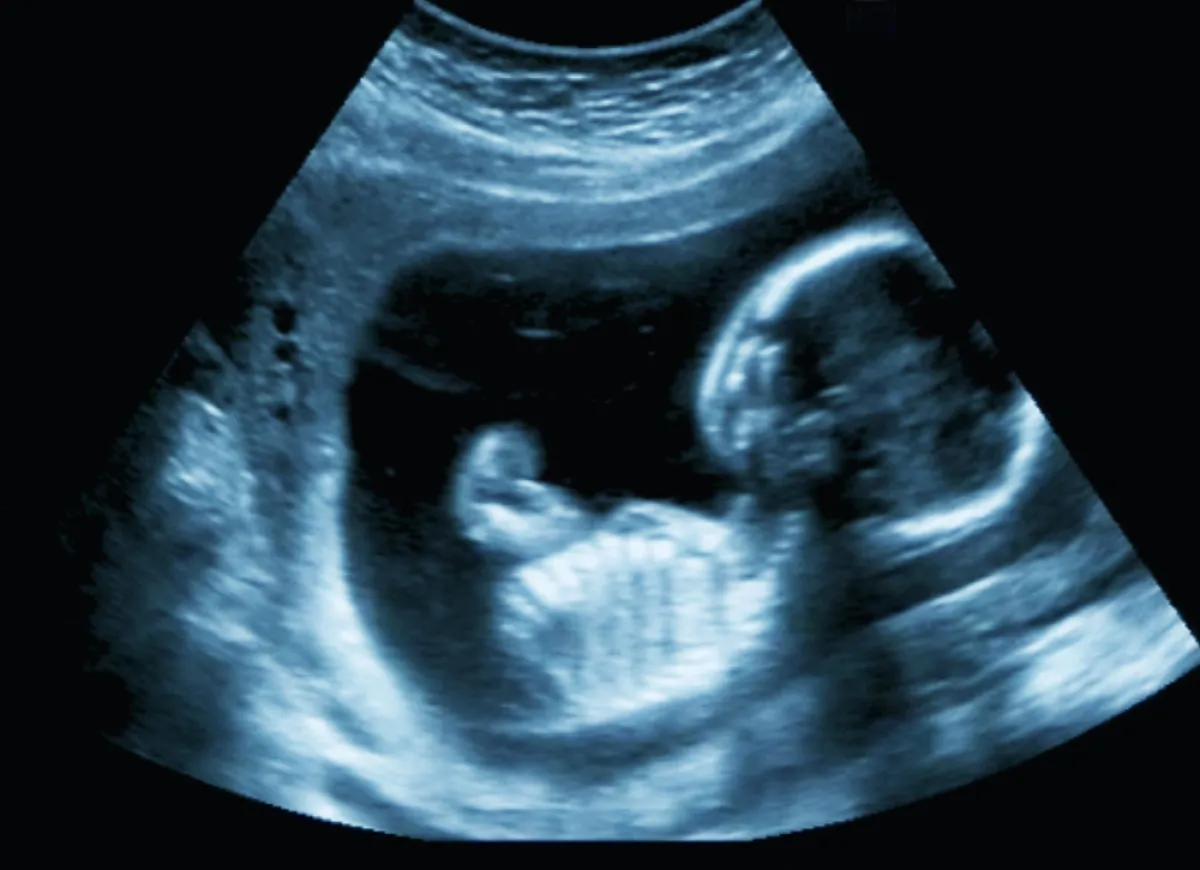

السونار يحدد نبضات الجنين، ويكون وسيلة الاطمئنان الآمنة للأم.

تقوم بعض السيدات بإجراء السونار مبكراً، ويكون النبض ضعيفاً وقد تشك بأن الجنين بلا حياة، ولذلك يخبرك الدكتور عدلي الحاج_ استشاري النساء والولادة_ بهذه الملاحظات حول نبض الجنين: